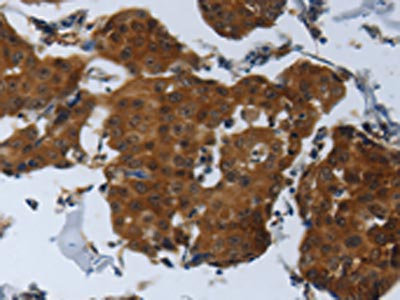

The image on the left is immunohistochemistry of paraffin-embedded Human breast cancer tissue using CSB-PA919263(SPAG4 Antibody) at dilution 1/25, on the right is treated with synthetic peptide. (Original magnification: ×200)